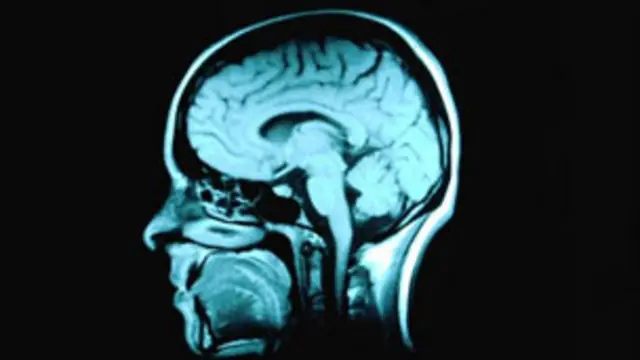

اسکن های مغناطیسی از مغزهای این افراد تغییراتی در بافت سفید مغز - قسمتی که دارای اعصاب مغزی است - نسبت به بافت مغزی افراد غیر معتاد نشان می داد.

محققان تحت سرپرستی دکتر هائو لی، یکی از اعضای آکادمی علوم چین، گفته اند که اختلالات در اعصاب بخشهایی از مغز که در احساسات، تصمیم گیری و اراده دخیل هستند مشاهده می شد.